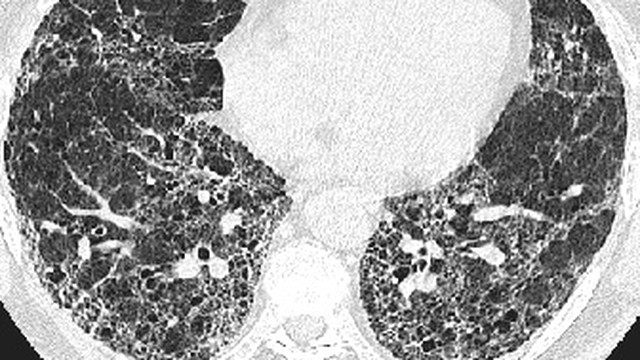

Xơ phổi là một tình trạng y tế nghiêm trọng, xảy ra khi mô phổi bị tổn thương và thay đổi cấu trúc dẫn đến việc mất khả năng cung cấp oxy hiệu quả cho cơ thể. Một trong những phương pháp phổ biến và hiệu quả nhất trong việc phát hiện bệnh là chụp X-quang xơ phổi. Hãy cùng Nhà Thuốc Long Châu tìm hiểu về thông tin này trong bài viết dưới đây.